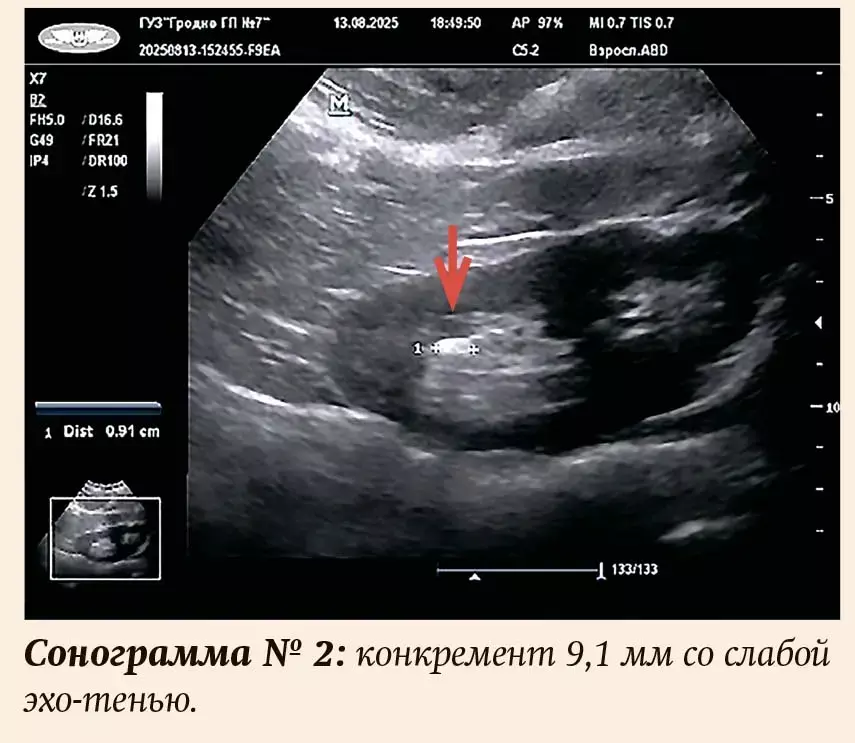

При исследовании в В-режиме конкремент представляет собой гиперэхогенную структуру округлой или овальной формы, за которой определяется акустическая тень, интенсивность последней зависит от размера и состава камня. Наличие акустической тени является важным диагностическим признаком!

Согласно большинству исследований, сложностей при выявлении достаточно крупных конкрементов (более 4 мм) обычно не бывает, но существуют ограничения в диагностике камней небольших размеров (2–3 мм) и уретеролитиаза.

Согласно литературным данным, конкременты различного химического состава выглядят неодинаково. Ураты и фосфаты определяются как яркие гиперэхогенные структуры, поэтому возможно обнаружить небольшие конкременты (3–4 мм). В то время как эхогенность оксалатных камней близка к эхогенности структур почечного синуса, и по этой причине обнаружить их при размере менее 6 мм часто затруднительно. Помимо этого акустическая тень у оксалатов даже при крупных размерах может отсутствовать, что еще больше затрудняет диагностику.

Размеры выявленных конкрементов — от 3,5 до 25 мм (см. примеры на сонограммах), причем у 5 пациентов (4,7 %) размер не превышал 4 мм. Во всех случаях даже при небольших размерах присутствовали все эхографические признаки конкремента, включая акустическую тень, иногда очень слабую, и/или мерцательный артефакт. Количество разнообразное — от одного до нескольких. Единичный конкремент присутствовал у 55 человек (51 %), у двух (2 %) — коралловидный, остальные имели 2 и более камней. У двух пациентов были выявлены признаки нефрокальциноза. У одной пациентки (57 лет) с несколькими конкрементами в обеих почках и рецидивирующим течением подтверждено наличие аденомы околощитовидной железы. У троих мужчин (2,8 %) с гиперплазией предстательной железы обнаружены камни в мочевом пузыре. Таким образом, проанализировав собственные данные, можно сделать вывод: полученные результаты соответствуют общемировой статистике.